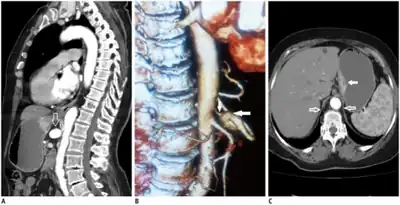

Further evaluation and confirmation can be obtained via angiography to investigate the anatomy of the celiac artery.[5] Historically, conventional angiography was used, although this has been largely replaced by less invasive techniques such as computed tomography (CT) and magnetic resonance (MR) angiography.[2][5] Because it provides better visualization of intra-abdominal structures, CT angiography is preferred to MR angiography in this setting.[5] The findings of focal narrowing of the proximal celiac artery with poststenotic dilatation, indentation on the superior aspect of the celiac artery, and a hook-shaped contour of the celiac artery support a diagnosis of MALS.[2] These imaging features are exaggerated on expiration, even in normal asymptomatic individuals without the syndrome.[2]

Proximal celiac artery stenosis with poststenotic dilatation can be seen in other conditions affecting the celiac artery.[2] The hook-shaped contour of the celiac artery is characteristic of the anatomy in MALS and helps distinguish it from other causes of celiac artery stenosis such as atherosclerosis.[2] This hooked contour is not entirely specific for MALS however, given that 10–24% of normal asymptomatic individuals have this anatomy.[2]

Median arcuate ligament syndrome-a)Stenosis and aneurysm of celiac artery because of compression arrows b)severe stenosis and poststenotic dilatation white arrow c) median arcuate ligaments arrows and gastric mucasal thickening

Coeliacus compression